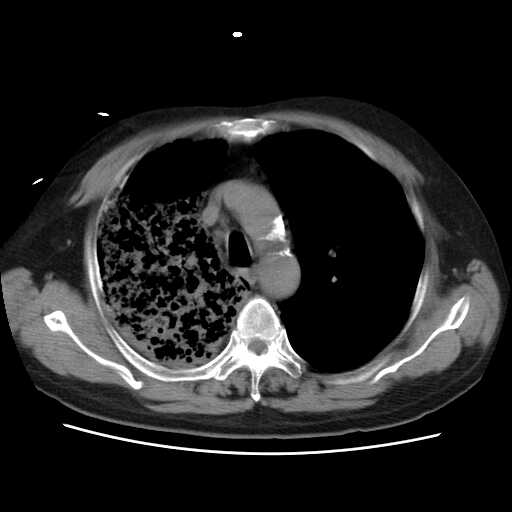

病变从8.11-8.17明显改变,增多,以蜂窝状改变为主,类蜂窝肺,似弥漫性肺泡癌,但是病变进展太快,不符合弥漫性细支气管肺泡癌。因此考虑为特殊微生物感染,多以霉菌类常见,建议细菌微生物学检查。

疑点二:影象表现怪异,大片阴影内见多发筛孔征,如何解释.

间质为主,血管炎性水肿?

结合临床慢支炎肺气肿,肺心病病史,三次胸片观察可见病情发展变化迅速,病情凶险,考虑多重感染伴ards.